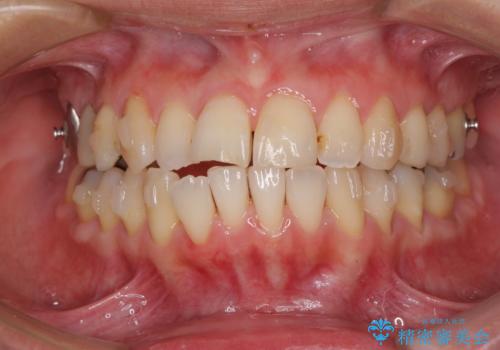

切端咬合をインビザライン矯正で解消

- 前歯のデコボコを気にして来院された患者様です。

上下前歯の先端同士が接触する切端咬合であったため、上顎は歯列を拡大し、下顎はIPR(歯と歯の間を削る)により叢生を解消しながら歯列を小さくすることとしました。

矯正装置にはインビザラインを用いることとしました。

治療途中に前歯に歯髄充血を思わせる痛みが認められたため、無理のない歯の移動と頻繁な経過観察を行いました。

切端咬合はスムーズに解消され、前歯の負担を軽減させることができました。